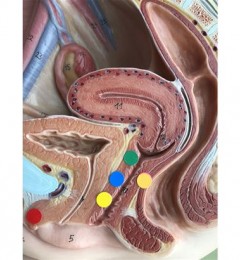

很多孕妈妈都会发现,自从怀孕后,身体好像不如以前那么好了。隔三差五的,一不小心就感冒咳嗽,要不就是头疼脑热血压高,这是怎么回事呢?其实,这是免疫力降低引起的。那么,为什么怀孕后免疫力会降低呢?主要有这几个原因:

孕妇荷尔蒙影响:免疫力主导我们体内与坏物质对抗的机制,能保护健康消灭不正常的细胞与感染源入侵,对孕妈咪来说,怀孕会因体内荷尔蒙的变化,让免疫系统顺势下降,以让母体不会因此“排斥”胎儿。